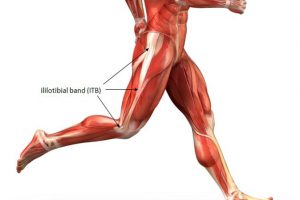

前置きが長くなりましたが、階段を下る時にひざが痛む多くのケースがひざのお皿の下にある「膝蓋下脂肪体(しつがいかいぼうたい)」が硬くなってしまっていることが考えられます。